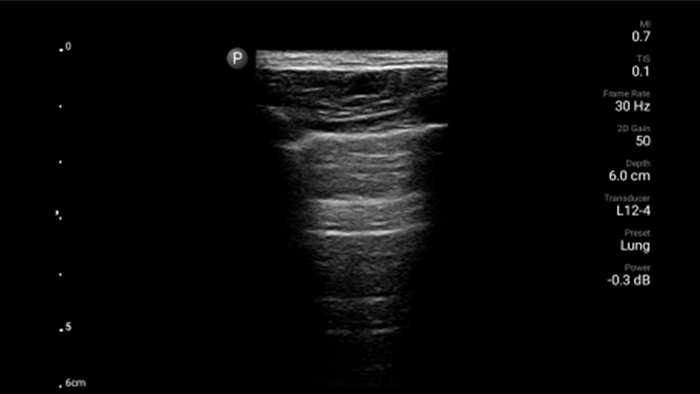

Exceptional ultrasound imaging

Lumify handheld ultrasound offers images that enhance diagnostic confidence.

See more when it counts

Lumify can help you make real-time decisions with more confidence, from assessment to recovery. Reveal the subtle details of an image, uncover enriched tissue definition with multiple angles and much more.